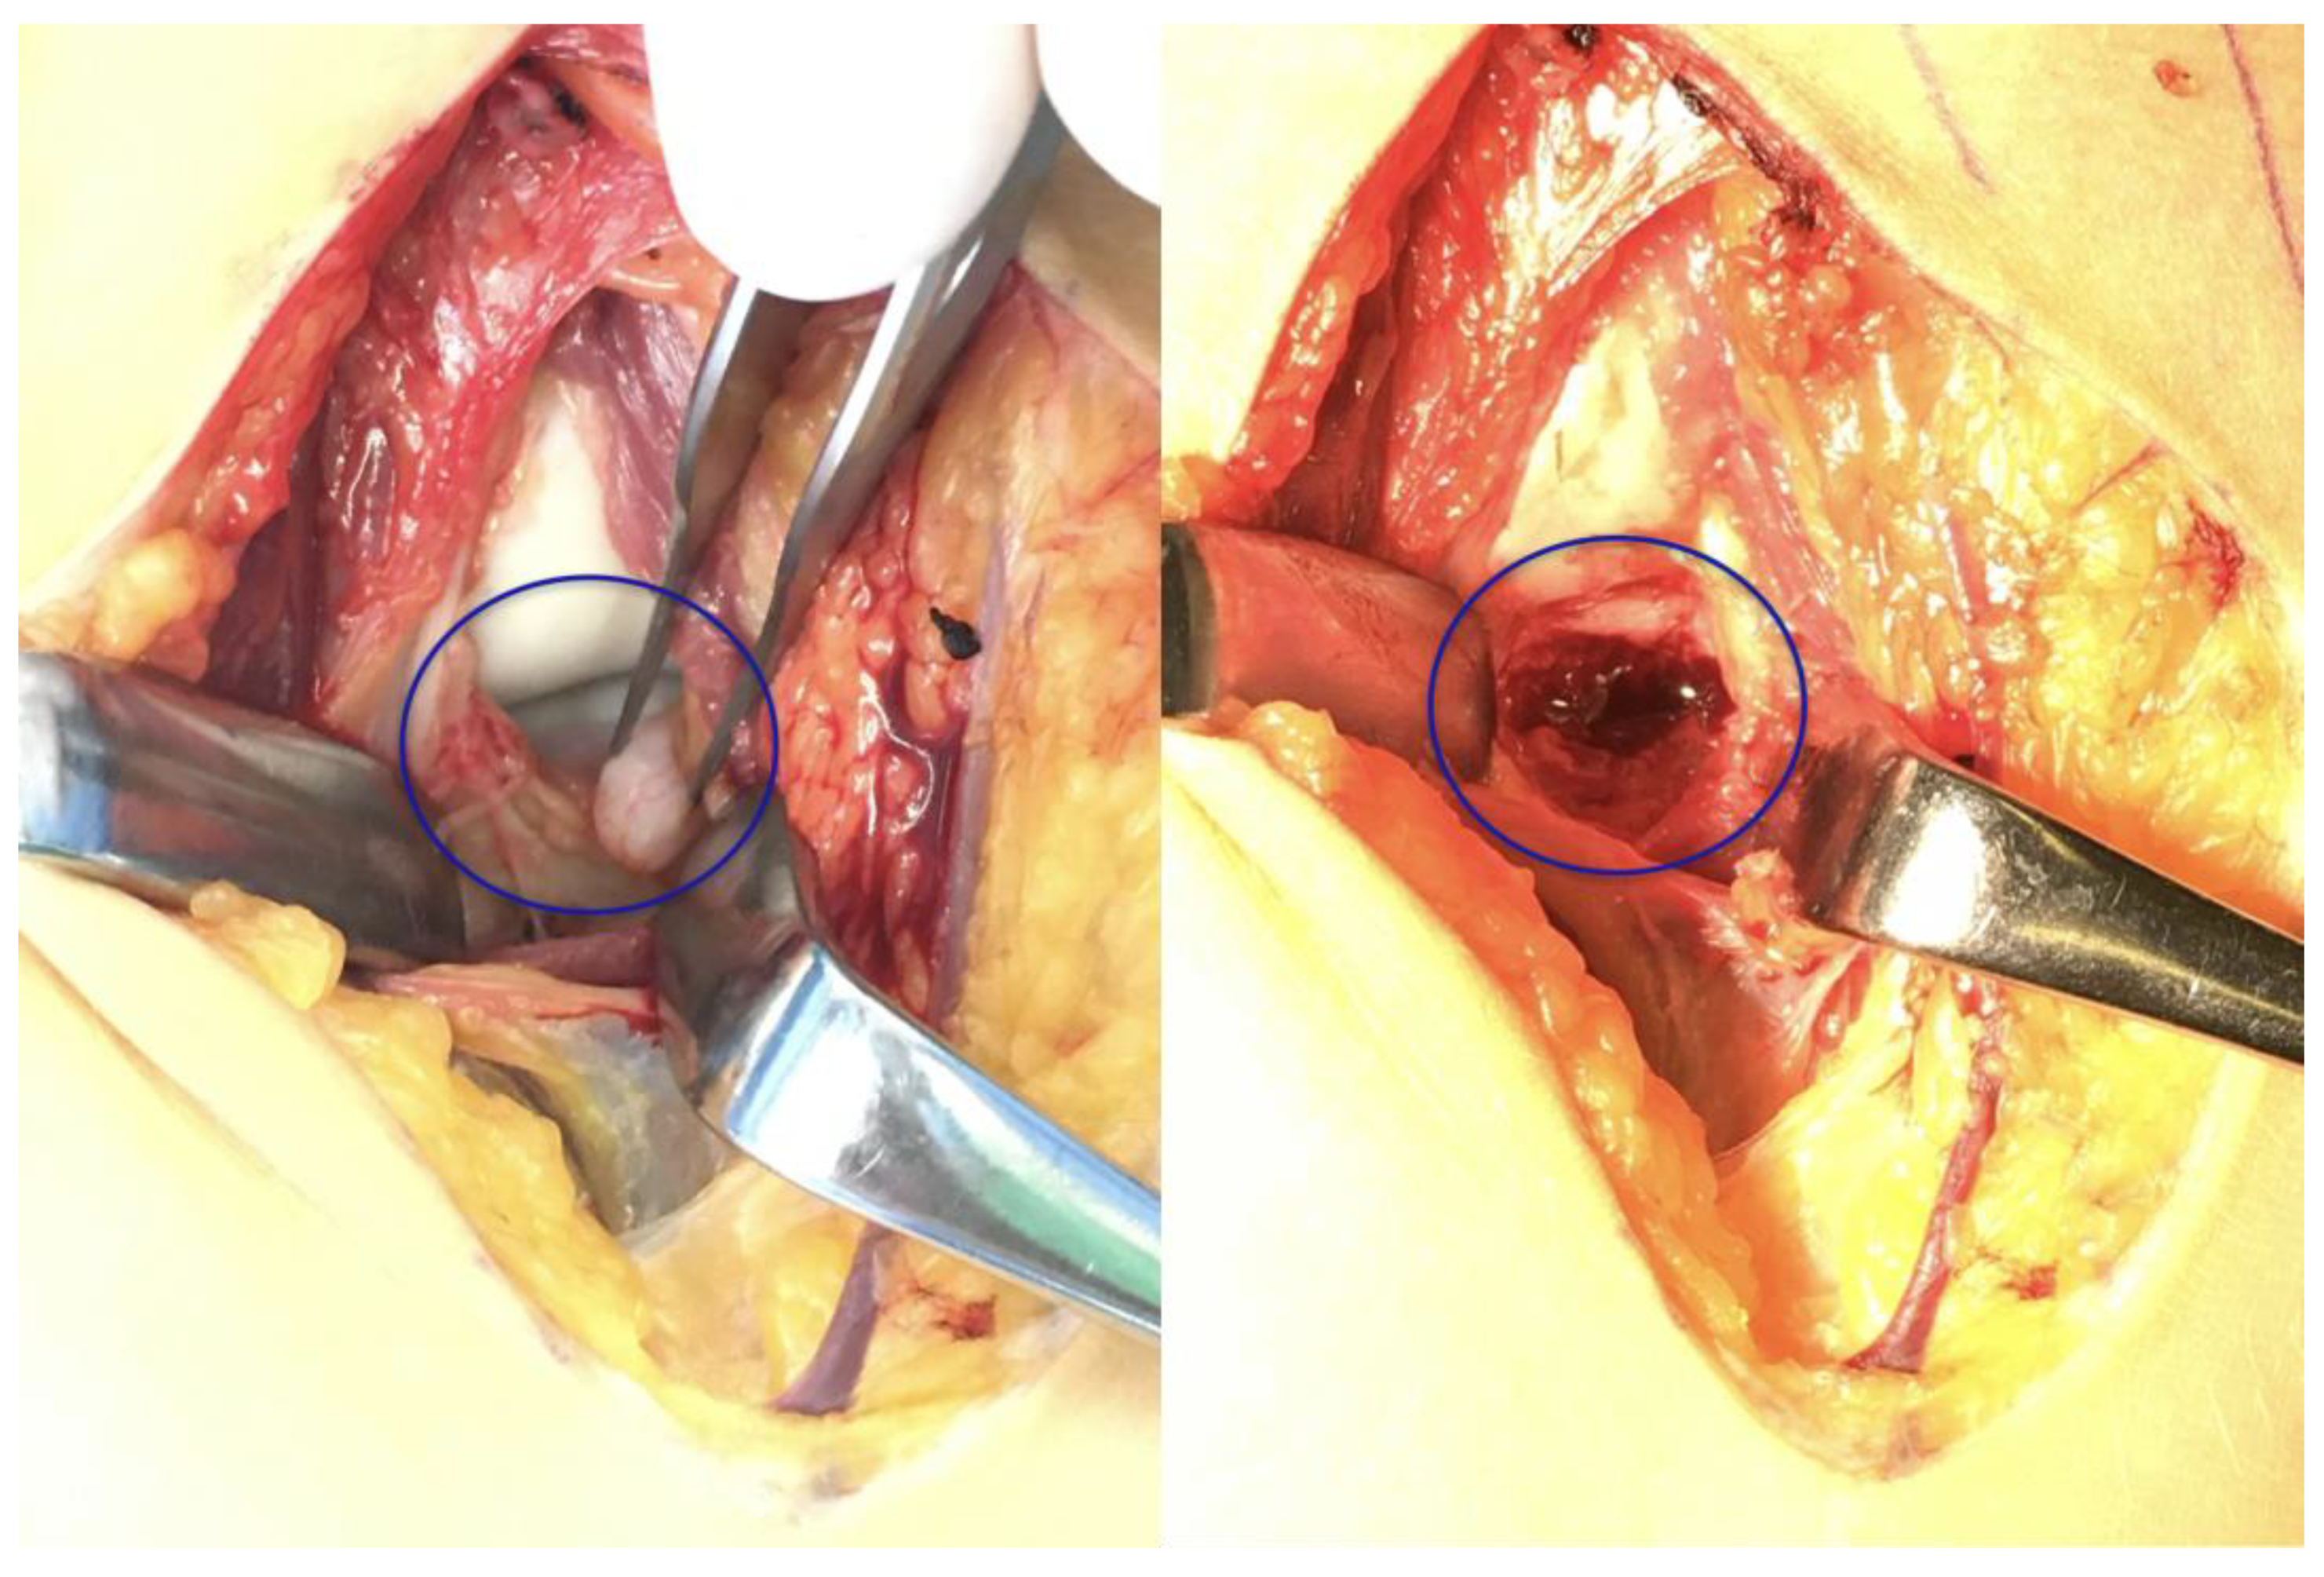

Figure 7.

Intraoperative images highlighting the separate bone fragment and the defect (blue circle).